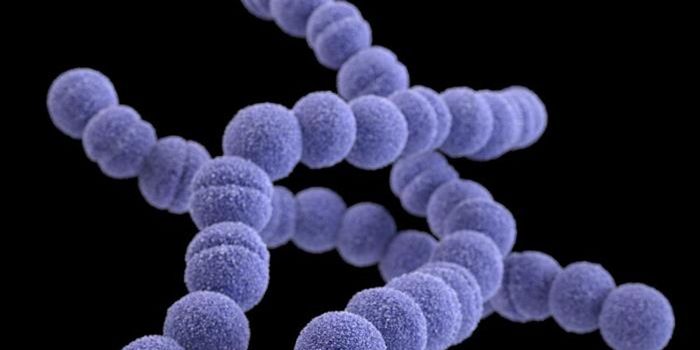

MAR 05, 2023MicrobiologyEstimates vary, but Streptococcus pyogenes infections may be responsible for the deaths of over 500,000 people every yea ...

SEP 12, 2019MicrobiologyStreptococci are a group of Gram-positive microbes that include pathogens that can cause mild and serious infections.